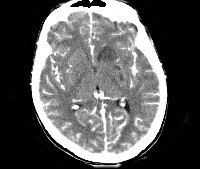

• КТ, МРТ головного мозга. Определяется утолщение, уплотнение оболочек мозга, диффузные изменения церебральных тканей. Наличие воспалительных очагов визуализируется не всегда. При паразитарной этиологии характерны округлые очаги гетерогенной структуры с кольцевидным усилением по периферии.